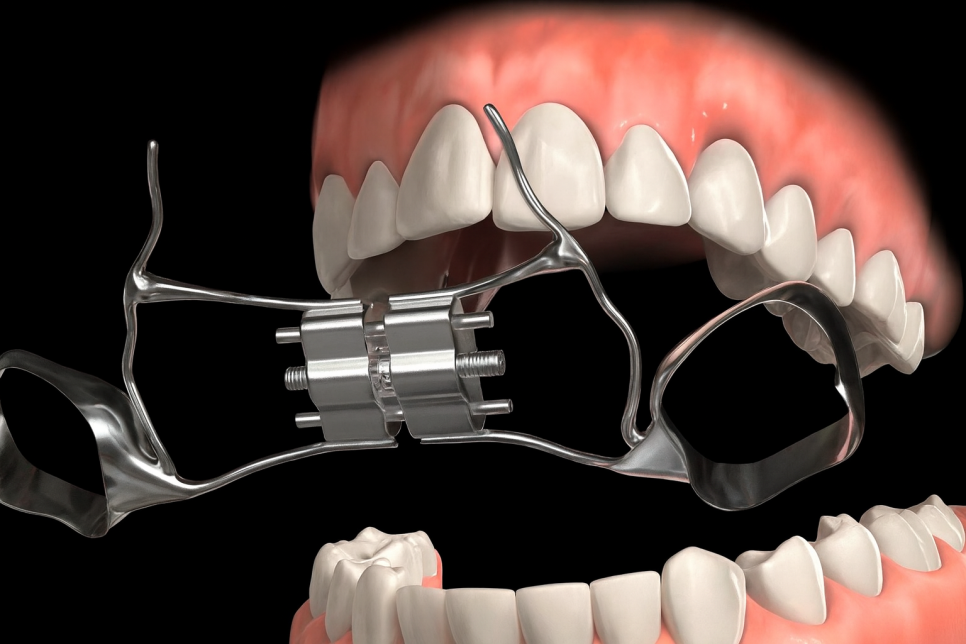

장치를 사용해서 윗턱 뼈 가운데에 있는

정중구개봉합 사이를 넓혀 골조직이 차오르게 함으로써

턱뼈를 넓혀주는 과정을 말합니다.

그 과정에서 사용할 수 있는 장치는

크게 고정식과 가철식으로 나누어집니다.

내발산 치과 에서 준비한 사진 속 밴드처럼 생긴 부분에

불소가 함유되어 충치가 예방 효능이 있는

파란색 접착제를 붙여 고정하는

Bonded RPE 사진을 준비해 봤습니다.

더불어 반치처럼 생긴 링을 치아에 끼우는

Band를 사용하는 일반적인 RPE 사진입니다.

이렇게 고정되는 장치와 꼈다 뺐다 하는 가철식

두 종류로 나뉘게 됩니다.

두 가지 장치 모두 가운데에 있는 나사를 돌려줘야

악궁 확장을 효율적으로 유도할 수 있습니다.

장치에 특수한 전용 키를 끼워준 후,

뒤쪽 화살표 방향으로 밀어 돌려줍니다.

이후 힘을 풀고 천천히 빼주면 됩니다.

보통 하루에 1~2회 돌리며

한번 돌릴 때 0.25mm씩 천천히 늘어납니다.